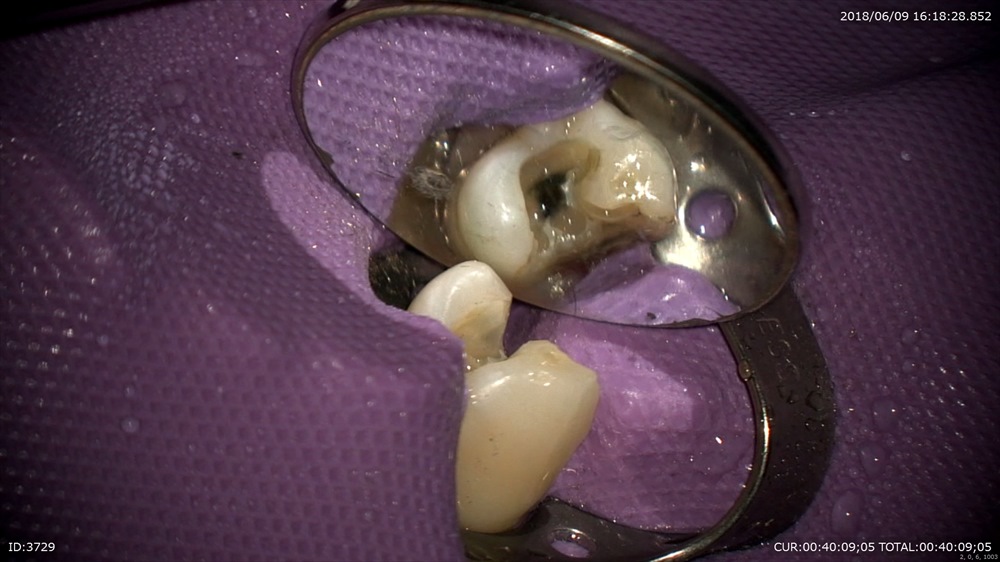

精密検査で

根尖性周囲炎と診断し

金属を外し根管治療

綺麗に無痛で

お薬をいれ今日は終了

このように再発を防ぐ為にすべての治療を精密に行っています。